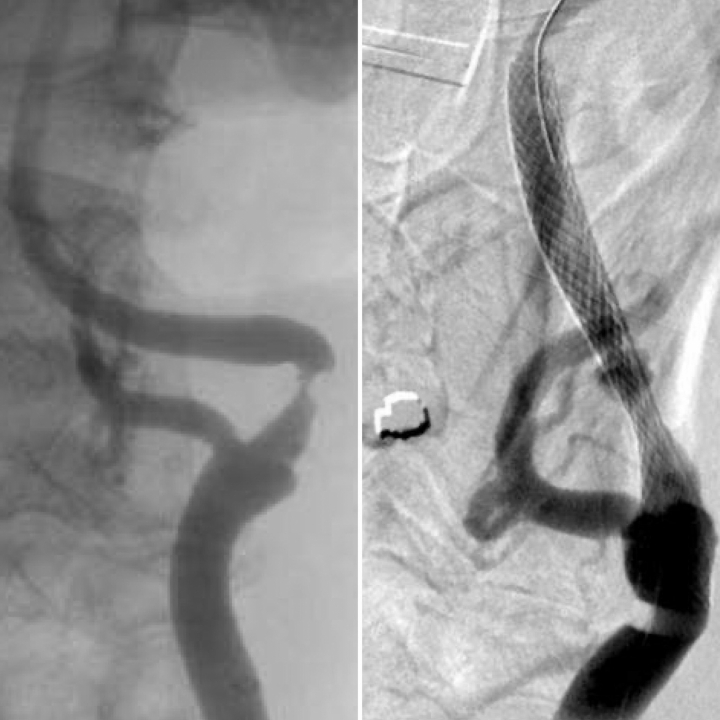

Para los ictus isquémicos podemos aplicar dos tratamientos diferentes: un fármaco por vena que intenta disolver el coágulo formado, pero que solo puede funcionar hasta las 4,5 horas desde que empiezan los síntomas. Y, la otra posibilidad, es la cirugía endovascular, un tratamiento que ha avanzado mucho en los últimos años que consiste en sacar el coágulo mediante catéteres, ya sea aspirándolo o cogiéndolo con una especie de pinzas. En este caso, el tiempo se amplía hasta las 24 horas desde la aparición de los síntomas, dependiendo de cada paciente.